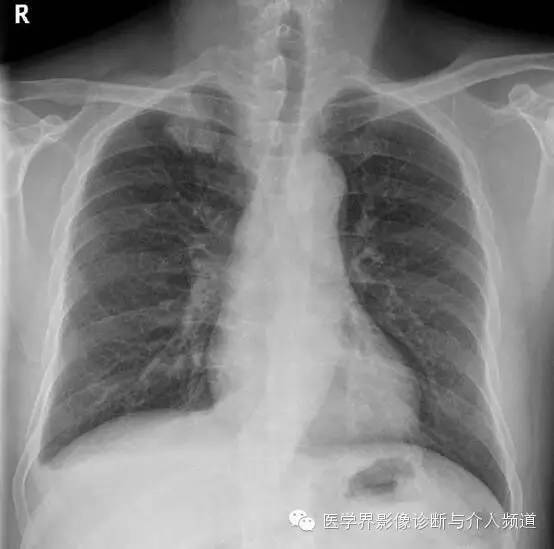

治疗前

CT显示右肺上叶实性团块病灶内不规则空洞形成,周围可见GGO,右侧胸腔少量积液。患者外周血嗜酸性粒细胞增多和Pw抗体阳性。治疗后X线平片显示右上肺结节影缩小。治疗前X线片显示病灶位于右肺上野,右侧肋膈角变钝。此外,X线平片示主支气管节段性偏心性狭窄,这是由于胸内甲状腺肿外在压迫所造成。